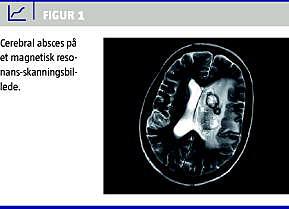

Under det første indlæggelsesdøgn fik patienten højresidig hemiparese og cerebral forværring med behov for intensivbehandling. En computertomografi af cerebrum viste en 3 cm stor proces i venstre hemisfære, og hun blev overflyttet til Rigshospitalet. En magnetisk resonans-skanning viste, foruden abscessen (Figur 1 ), septisk embolus i venstre arteria cerebri media. En ekkokardiografi var uden tegn på endokarditis.